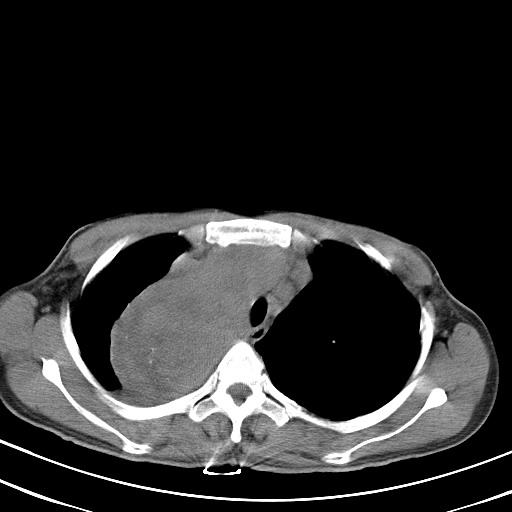

以下是引用汪涛同志在2007-8-2 0:40:00的发言:[br]病变虽然广泛,同时侵及双侧纵隔,但是无论左侧和右侧上下观察都是与右侧颈部甲状腺相延续的,而且强化幅度基本一致,又同时具有恶性病变病变的某些特征:肿块过大且密度不均,部分层面与正常纵隔结构分界不清,结合病史已有两年,考虑:胸内甲状腺肿恶变可能。[br]